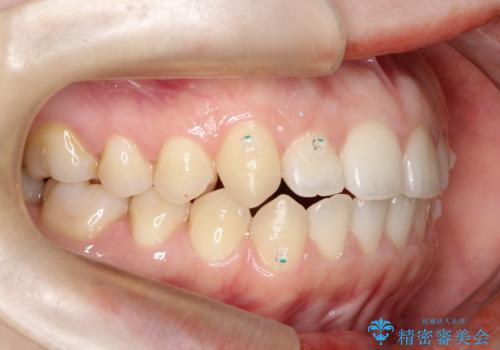

前歯のガタツキ、前歯の噛み合わせ(開咬)をインビザライン治療で治しました

- 前歯のがたつき、噛み合わせが気になるとのことで来院された患者様です。

インビザラインを使用して治療しました。

前歯がしっかり噛んでない状態(開咬)を治すために、前歯にゴムをかける必要があります。ゴムかけは患者様にご協力していただきます。